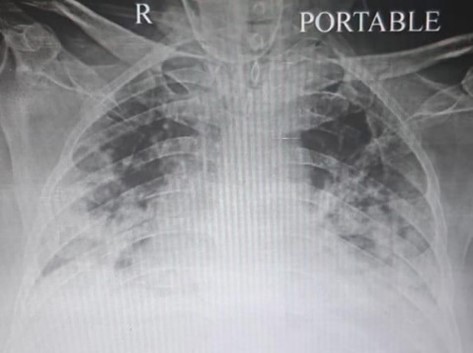

A sixty years old gentleman was brought to me with complains of breathlessness and low oxygen levels of 85%. He was admitted at other hospital for the treatment of COVID 19. Two days before he was discharged from that hospital after five days of treatment. He had history of heart disease and had undergone a procedure for the same. He responded to initial treatment but after a day of stabilization his condition deteriorated and I shifted him to ICU. His oxygen was falling rapidly and he was complaining of increasing uneasiness in breathing in spite of high flow of oxygen. I initiated support of noninvasive ventilation but oxygen level remained at 93%. He had spikes of fever and he became very sick. His oxygenation was becoming increasingly difficult and his heart rate and blood pressure were fluctuating. With ten days of rigorous monitoring and management, he showed improvement in his oxygen levels and blood pressure. He could be weaned from ventilator after almost twelve days. Another few days went uneventful but while he was stabilizing from this life threatening episode, on one morning he felt breathless again and his heart rate increased to 132 beats per minute. Now his breathing was deteriorating and oxygen was falling again. Increasing oxygen provision was not making any impact and he was again supported with BIPAP. His blood pressure decreased and he threw a new spike of fever. By then he was in ICU since twenty days. His lungs were significantly damaged and he was physically weak. There was a possibility of secondary infection in blood or lungs. At this stage secondary infections may prove fatal. Broad spectrum antibiotics to cover multi drug resistant organisms were considered. After almost five days of intensive treatment he showed improvement. I could wean him from ventilator. Now he was able to breath with moderate oxygen supply. He had no fever spikes. However his heart was beating fast. His 2D ECHO revealed mild reduction in pumping but nothing significant. He improved further and transferred to ward after few days. He kept improving in room and after forty days of hospital stay he was discharged. He is now recovering at home.

X RAY